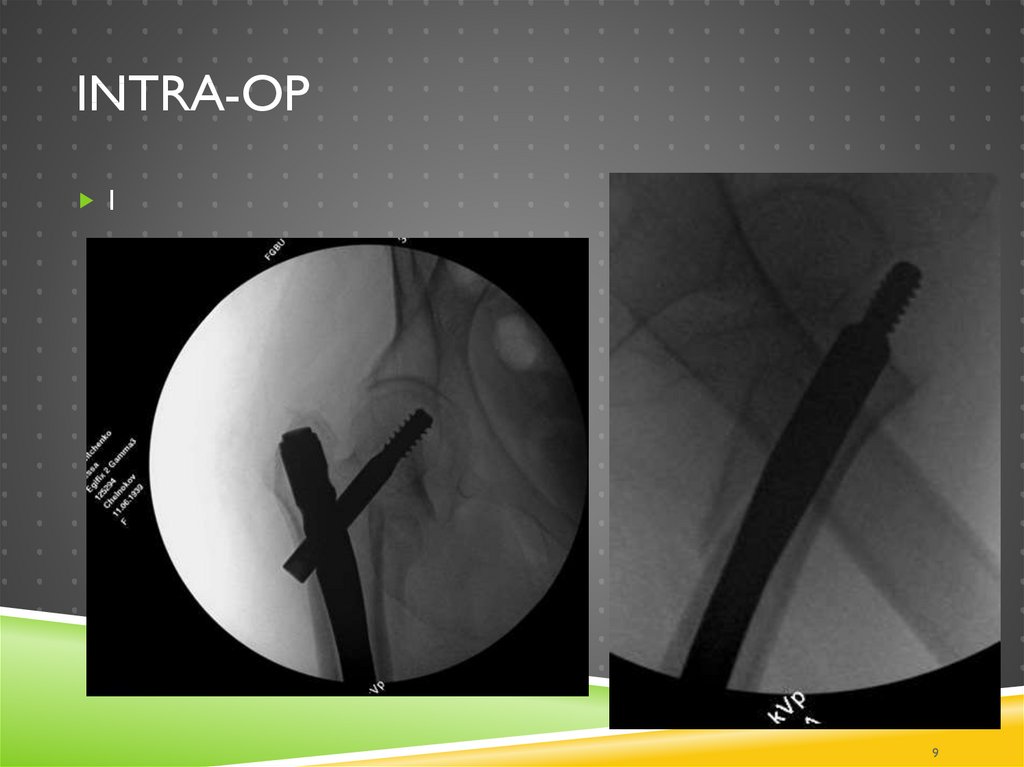

10. Intra-op

INTRA-OP

10